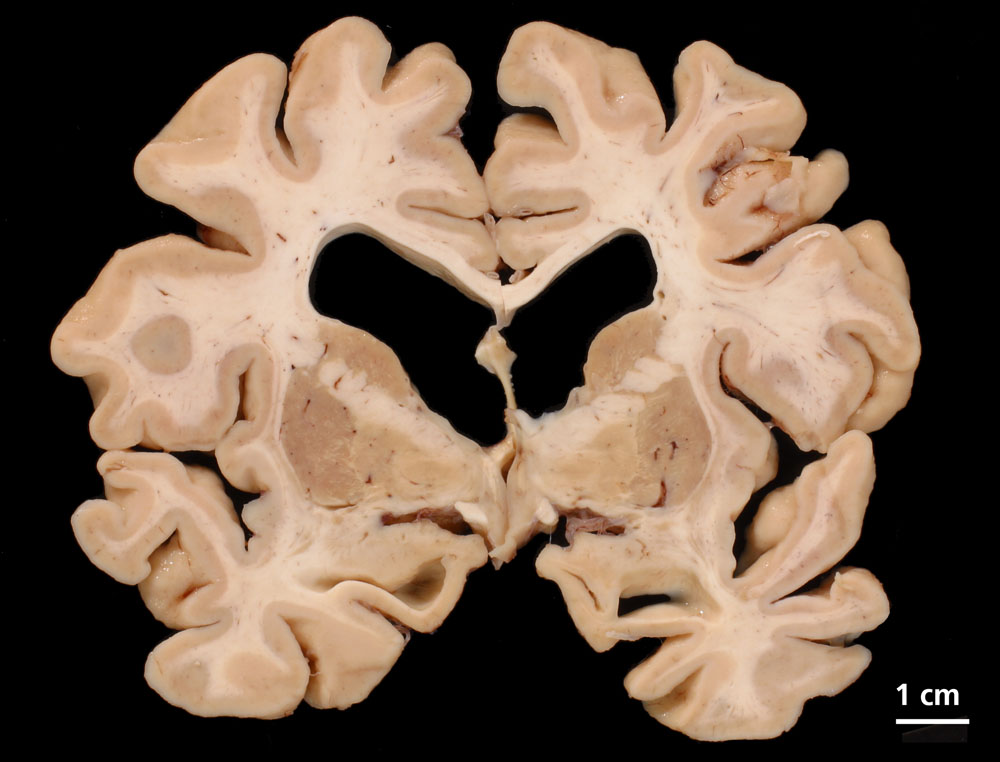

Gehirne von Alzheimer Patienten sind makroskopisch durch eine kortikale Atrophie (vor allem temporo-parietal) charakterisiert. Weiter findet sich meist eine deutliche Atrophie von Hippocampi und Mandelkernen. Diese geht einher mit einem Hydrocephalus internus (e vacuo), wobei vor allem die Temporalhörner der Seitenventrikel betroffen sind.